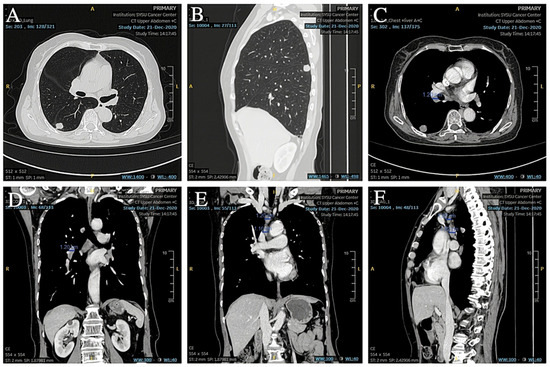

Based on the patient’s medical history and the results of the puncture biopsy examination, we diagnosed this patient with hilar lymph node metastasis from SCLC combined with a rare EML4-ALK fusion gene mutation. Due to the patient’s refusal to undergo chemotherapy, ensartinib was chosen as the first-line agent for targeted therapy. The patient was given 225 mg of ensartinib (Ensacove) orally once a day for two weeks, and after two weeks of treatment, a repeat CT showed that multiple lymph nodes in the mediastinal region had partially shrunk compared to before. Since the patient developed symptoms of drug rash (CTCAE grade 4) within two weeks of the first dose, we adjusted the dose to 200 mg daily and continued treatment for two weeks. A repeat CT two weeks later (34 months postoperatively) suggested that multiple lymph nodes in the mediastinal region continued to shrink from the imaging two weeks earlier (Figure 9A,B). As this patient showed a trend toward improvement on imaging after a month-long course of ensartinib, we elected to continue treatment at ensartinib 200 mg daily for this patient. As of 8 December 2023 (36 months postoperative), the patient’s hilar lymph node had shrunk to a smaller short diameter of 19 mm (Figure 9C–F). The patient still received ensartinib and the cutoff time for documenting the condition in this case report was 31 January 2025 (49 months postoperative). The patient achieved a PFS of more than 12 months with ensartinib.

Figure 9. (A,B) CT showed that the hilar lymph nodes were smaller than before. (CF) CT showed that the short diameter of hilar lymph nodes was reduced to about 19 mm, and other mediastinal lymph nodes were also reduced from the previous size.